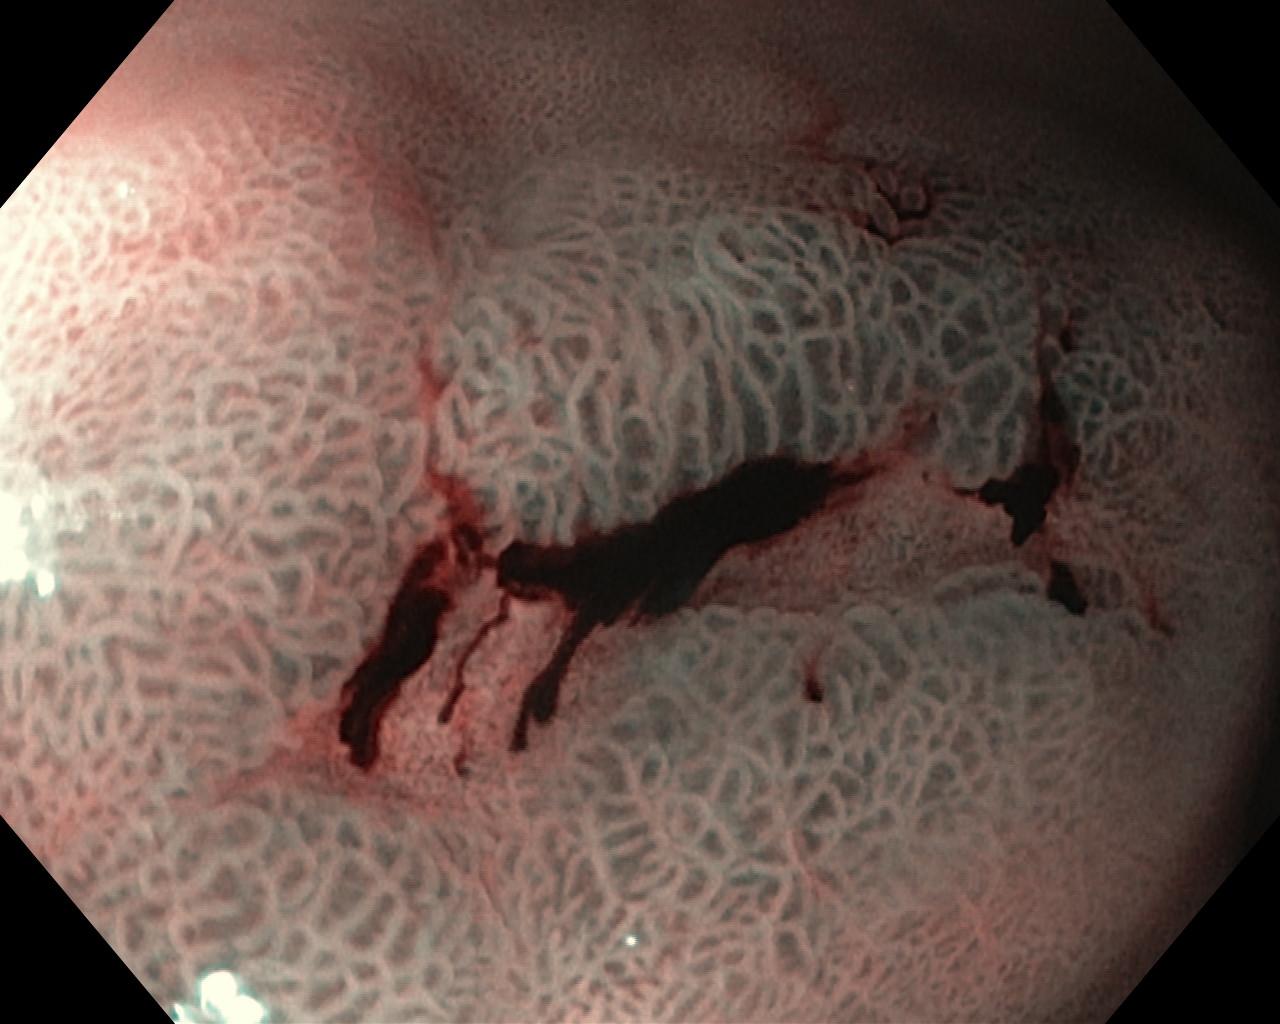

Krwawienie